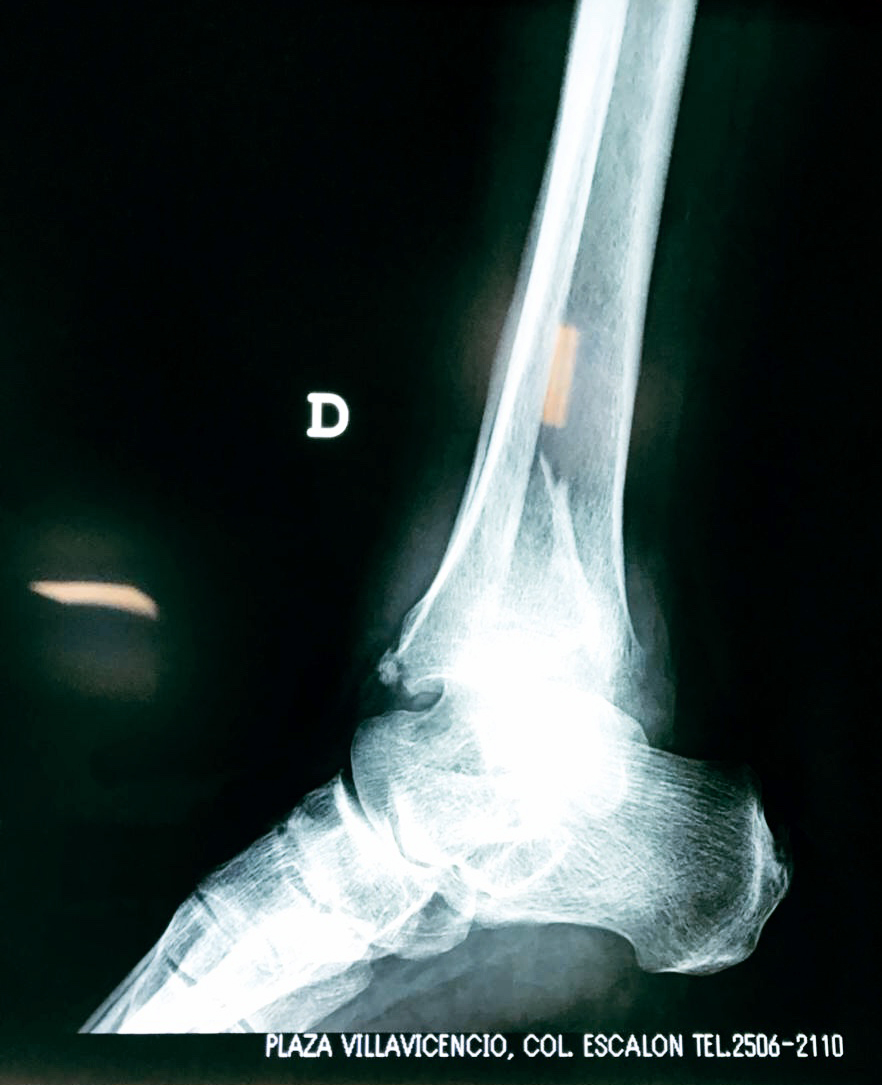

Una fractura de tobillo es la rotura de uno o más de los huesos del tobillo. Estas fracturas pueden ser:

- Parciales (el hueso está sólo parcialmente fisurado, no del todo).

- Completas (el hueso está perforado y está en 2 partes).

- Producirse en uno o ambos lados del tobillo.

Algunas fracturas de tobillo pueden requerir cirugía si:

- Los extremos de los huesos están desalineados entre sí (desplazados).

- La fractura se extiende hasta la articulación del tobillo (fractura intra-articular).